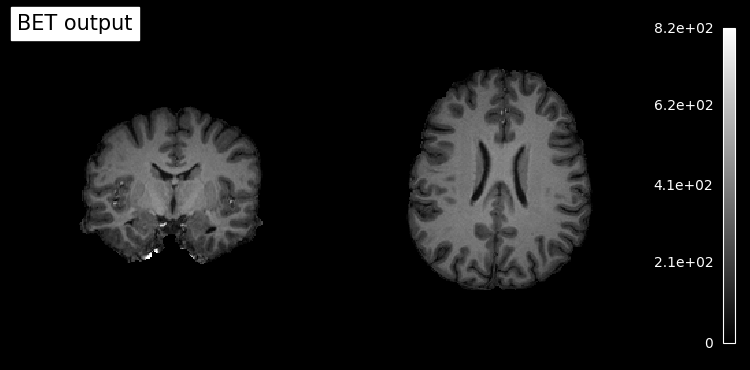

# Plot original input file

plotting.plot_anat(input_file, title='BET input', cut_coords=(10,10,10),

display_mode='ortho', dim=-1, draw_cross=False, annotate=False);

# Plot skullstripped output file (out_file) through the outputs property

plotting.plot_anat(res.outputs.out_file, title='BET output', cut_coords=(10,10,10),